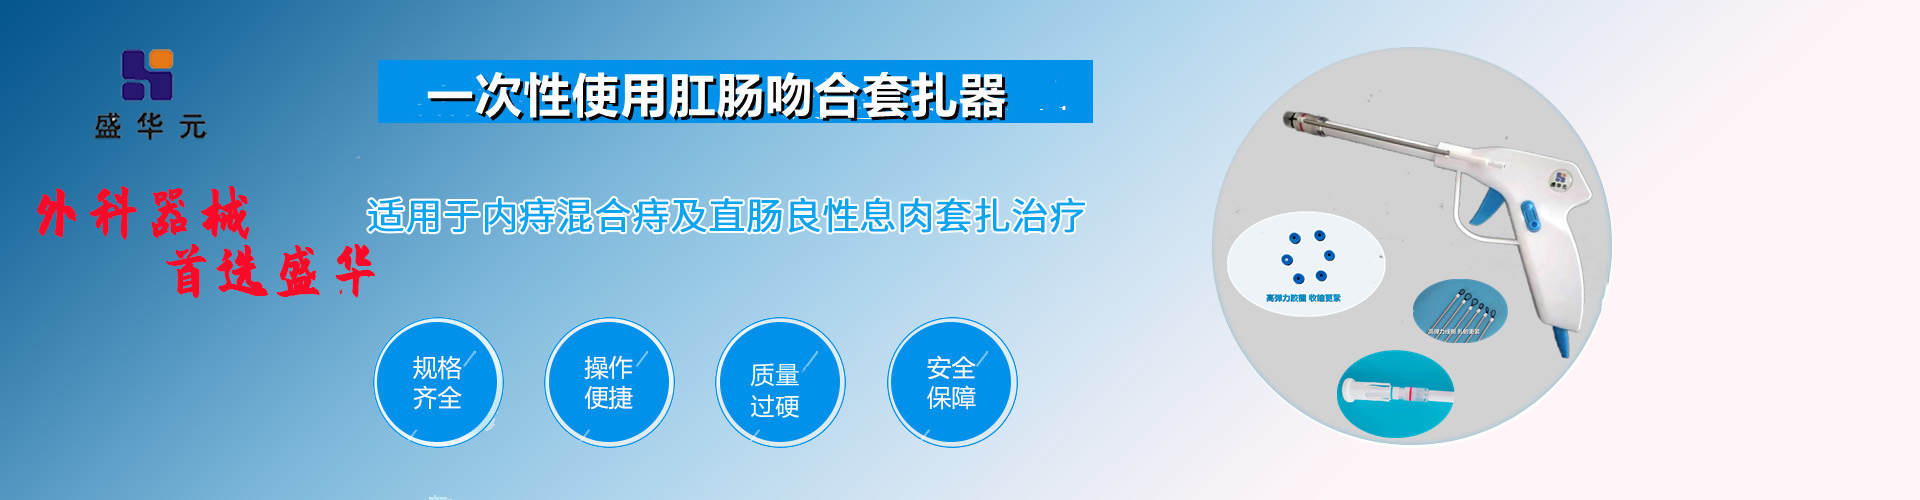

一次性使用肛腸套扎器

大腸息肉的處理原則是發(fā)現(xiàn)息肉即刻摘除。目前摘除息肉的方法主要有內(nèi)鏡下行各種摘除法。 根據(jù)息肉的形態(tài)、大小、數(shù)量和蒂的有無(wú)、長(zhǎng)短粗細(xì)而分別采用: ①高頻電...詳情>>